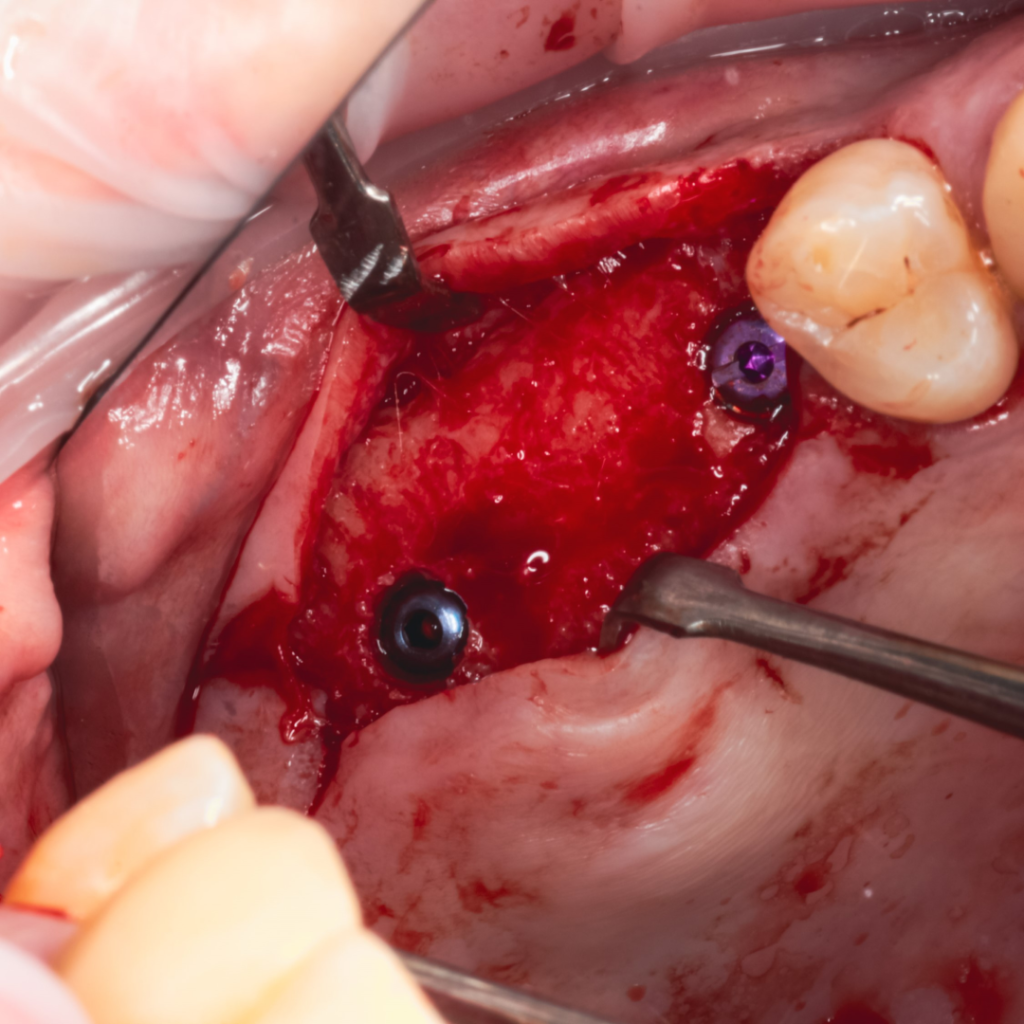

Плановая имплантация в жевательном отделе перед тотальной реабилитацией с поднятием прикуса.

По результатам диагностики принято решение установить имплантаты AnyRidge и AnyOne с использованием хирургических шаблонов Bonepen 3D.